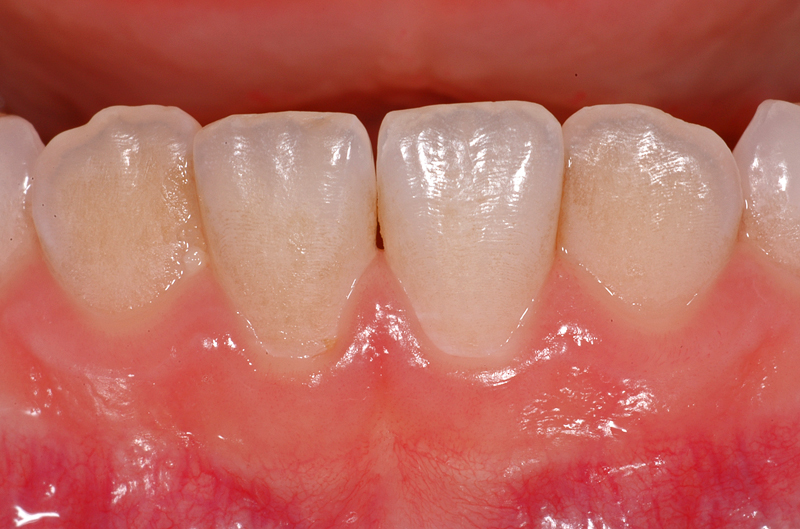

Hier ein weiterer Fall mit weissen / gelblichen Flecken an einem unteren linken mittleren Schneidezahn (Zahn 31). Diese Flecken gehen gegen den Zahnfleischrand ins Gelbliche über. Die grossflächigen Flecken auf der Zahnaussenseite sind durch eine Zahnschmelzbildungs-Variation bedingt und «im Zahn drin».

Zudem hat der Zahn 31, wie die anderen auch, braune Auflagerungen im Bereich der Zahnzwischenräume. Diese Verfärbungen lassen sich in der Regel gut reinigen und entfernen.

Ebenfalls gut sichtbar auch hier die Perikymatien (die Querrillen).

- Weisser / gelblicher Fleck an einem 31